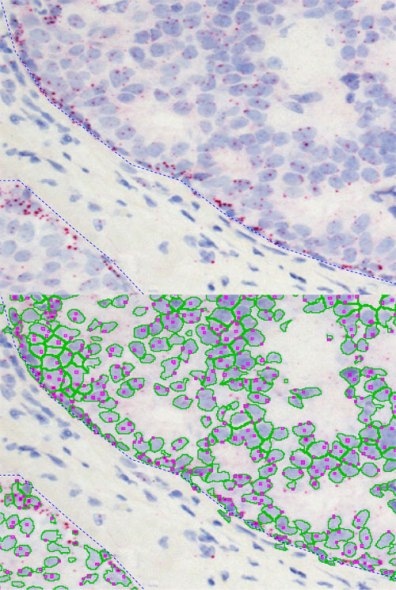

The following examples show Backward Gating versatility on segmented nuclei positive for Ki-67. Backward gating can be done for any measured parameter on histograms and scattergrams.

In the second example backward gating is used to visualise cells in which the Her-2NEU staining, detected with the skeleton algorithm, has a closure angle of more than 180 degrees.

The nuclear segmentation algorithm is highly efficient in difficult situations in tissue and can be set with two values only - mean nuclear size and nuclear channel background threhshold. The cell compartment algorithm provides a large amount of flexibility with a few simple settings (see below, yellow=segmented nuclei, blue nuclei positive for DAB or cytoplasm positive for Permanent Red marker).

The skeleton algorithm permits the detection of membrane stainings (see image above).